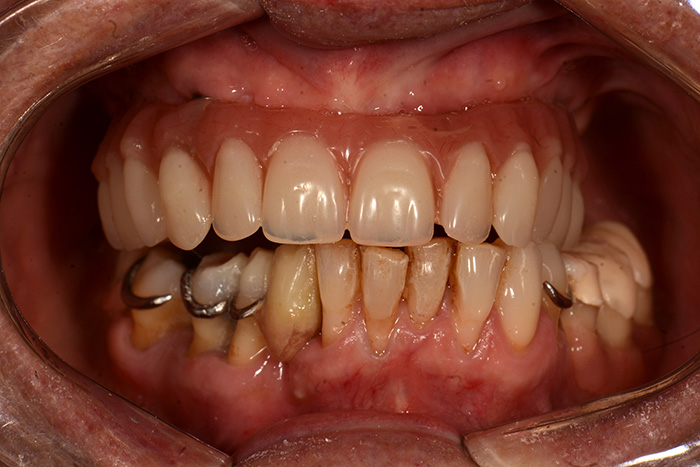

Fig. 18 : Mise en place le soir même de la chirurgie d’une prothèse provisoire transvissée.